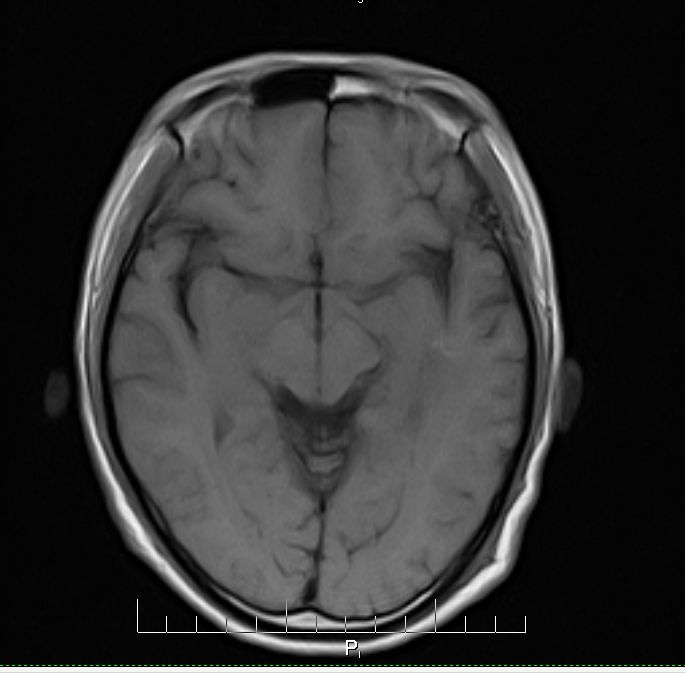

标题: MRI2379:30岁,男,癫痫10年,请各位看一下;CT示:左颞叶钙 [打印本页]

标题: MRI2379:30岁,男,癫痫10年,请各位看一下;CT示:左颞叶钙

左颞叶区见不规则点状混杂信号影

支持2楼 左颞叶区见不规则点状混杂信号影,考虑动静脉畸形。

考虑左侧颞叶脑血管畸形(avm)。----t1低等高混杂信号,t2等高信号周边较多流空血管影[冠状位明显],mra左侧大脑中动脉受压,远侧聚集.